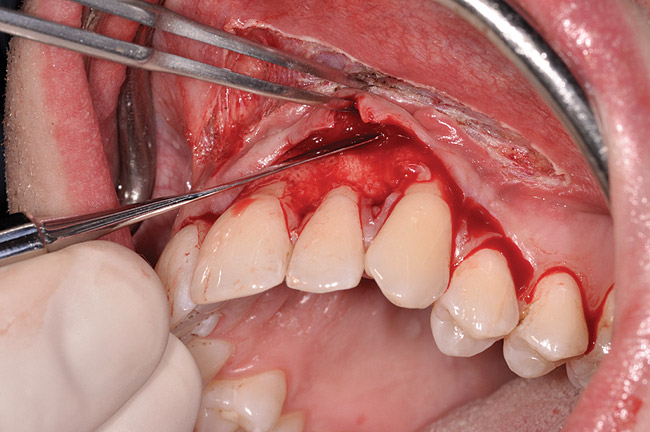

After administration of an appropriate local anesthetic, a laser-assisted split-thickness vestibuloplasty was performed superior to the mucogingival junction from the right central incisor to the left first premolar region (Figure 7). Prior to any incisions being performed, a 20-mm x 40-mm dermal matrix graft (Puros Dermis), a 0.8-mm to 1.7-mm thick piece of tissue, was trimmed to appropriate length and width to correct the gingival defect present (Figure 8). The tissue graft was sized to 6 mm in height and spanned to the mesial line angle of the left central incisor to the distal line angle of the left canine area. The dermal matrix graft was rehydrated with the patient’s own platelet-rich plasma solution, which was harvested from 20 cc of whole blood collected immediately prior to the surgical procedure (Figure 9).

After initial incision techniques were done, a papillary-sparing incision was performed, leaving the crest of the papilla intact (Figure 10), thus allowing flap closure to be accomplished with a bed of autogenous tissue to support revascularization of the dermis/buccal flap complex. A full-thickness flap was then elevated to the mucogingival junction, after which a split-thickness dissection with a blunt elevator superior to the mucogingival junction area was performed to allow for release of tension and to let the buccal flap be mobilized coronally at closure (Figure 10). Care must be taken to avoid perforating the tissue in the region of the vestibuloplasty incision. After tension-free release of the flap, root planing of the exposed root surfaces was accomplished, followed by removal of the smear layer of cementum and chemical detoxification with a citric acid solution pH1 applied over the previously root-planed surfaces. After root preparation, the keratinized papillary tissues that remained following initial incisions were de-keratinized by using a #4 round diamond on a high-speed handpiece. De-keratinization provided a wound bed that enabled the dermal matrix graft to be secured and supported revascularization of the coronally repositioned buccal flap at closure.

Fig 7. Laser-assisted split-thickness vestibuloplasty performed.

Figure 7